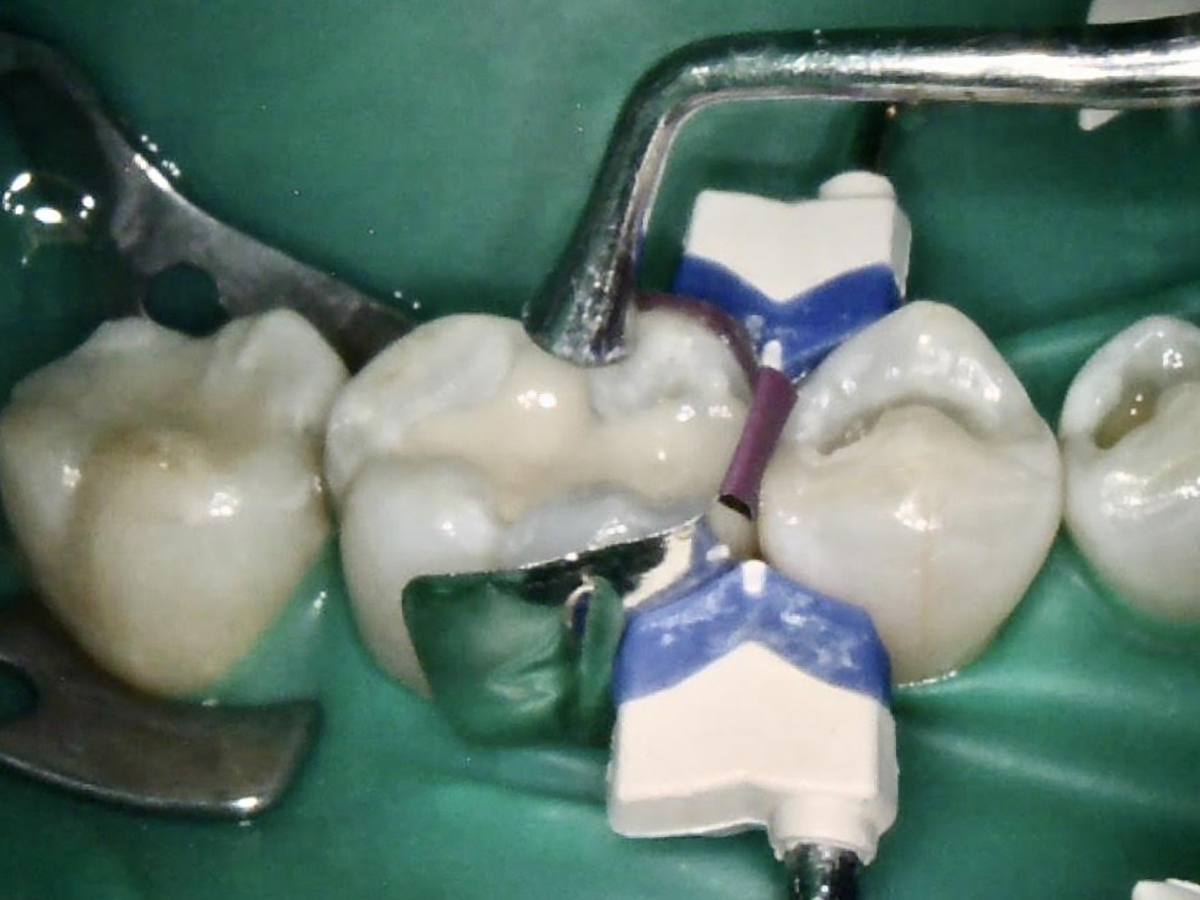

After a clean and neat cavity preparation, liner was placed on the deep cavity surface to mask the dark amalgam stain. The liner was light-cured for 20 seconds. A wide bevel was placed on the occlusal surface, and then a ring and matrix were placed. A selective enamel etching was performed with 37% phosphoric acid (Figure 3), rinsed, and dried. Universal bond was prepared by adding one drop from each bottle of the adhesive product into a mixing well and then briefly mixing. The bond was then placed (Figure 4) and air-dried with low air for 5 seconds, then with stronger air for another 5 seconds. No light-curing was needed for this bonding system. Then, one-shade composite was placed in small increments using a condenser. Before light-curing, some occlusal anatomy was created using hand instruments, including an acorn-shaped burnisher (Figure 5) and blue titanium CIB3. The occlusal adjustments and more detailed anatomy were created using a football-shaped diamond bur and a needle-shaped diamond bur. The final finishing and polishing were done using a large, coarse disc, a fine-needle diamond bur, and white Arkansas stone. A postoperative photograph (Figure 6) showed how the restoration blended naturally with the tooth. Figure 7 and Figure 8 feature a bitewing x-ray and photograph of the tooth taken during the 6-month recall examination.

Fig 3. Selective enamel etching on tooth.

Figure 3

Fig 4. Universal bond was placed and lightly air-dried.

Figure 4

Fig 5. Occlusal anatomy was created using hand instruments and an acorn-shaped burnisher.

Figure 5